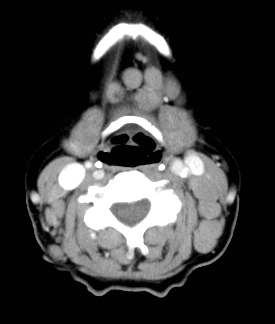

Hạch viêm ở cổ (Cervical adenitis)